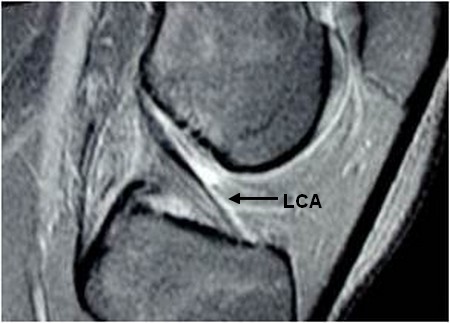

Разрыв капсульного аппарата

Разрыв капсульного аппарата 111 фото